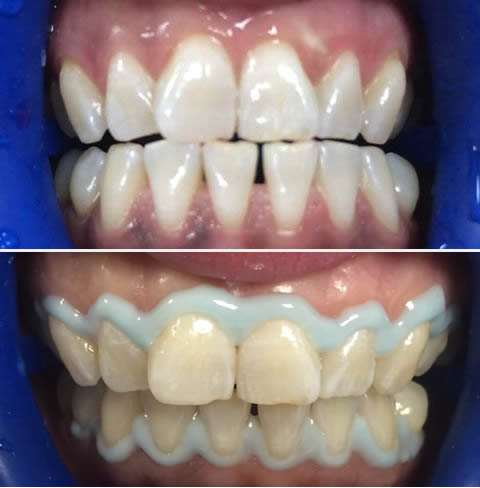

Ortodonti her yaşta kişiye uygulanabilen diş ve yüz düzensizliklerinin teşhis ve tedavisi ile ilgilenen diş hekimliğinin bir alanıdır.